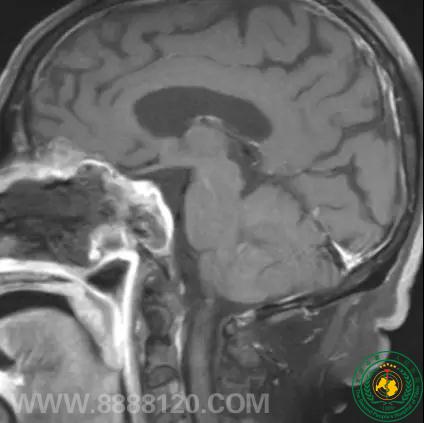

神经外一科完成四川省第一例经鼻神经内镜下蝶窦脑膜瘤切除术

神经外一科完成四川省第一例经鼻神经内镜下蝶窦脑膜瘤切除术18027